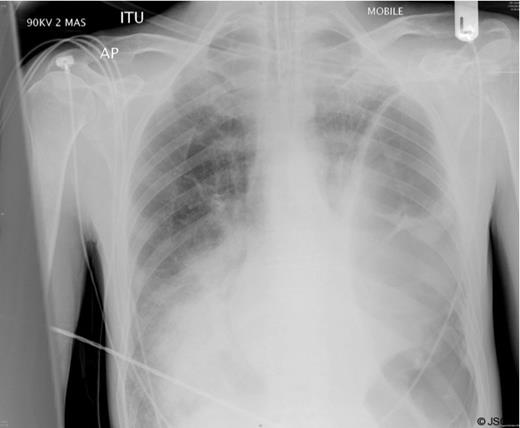

A chest radiograph (Figure 1) showed a large air filled structure within the left hemithorax, loss of clarity of the left hemidiaphragm and patchy consolidation of the middle and right lower lobes.

A clinical diagnosis of a possible spontaneous rupture of the diaphragm was made. The patient underwent an emergency laparotomy as he was not stable enough to undergo cross-sectional imaging to confirm the diagnosis. There were no abnormal findings at laparotomy. A left sided chest drain was immediately inserted with release of air under tension and pus (Figure 2).

In retrospect it is likely that this gentleman presented with a severe pneumonia complicated by a contained tension pneumothorax within an empyema cavity caused by positive pressure ventilation.

The clinical presentation of a tension pneumothorax is often similar with severe cardio-respiratory compromise and the patient in extremis. It is a well recognised complication of positive pressure ventilation with or without associated lung disease (4). The plain radiographic appearances of these two conditions are also similar with both conditions associated with air filled cavities within the thorax with or without mediastinal shift.